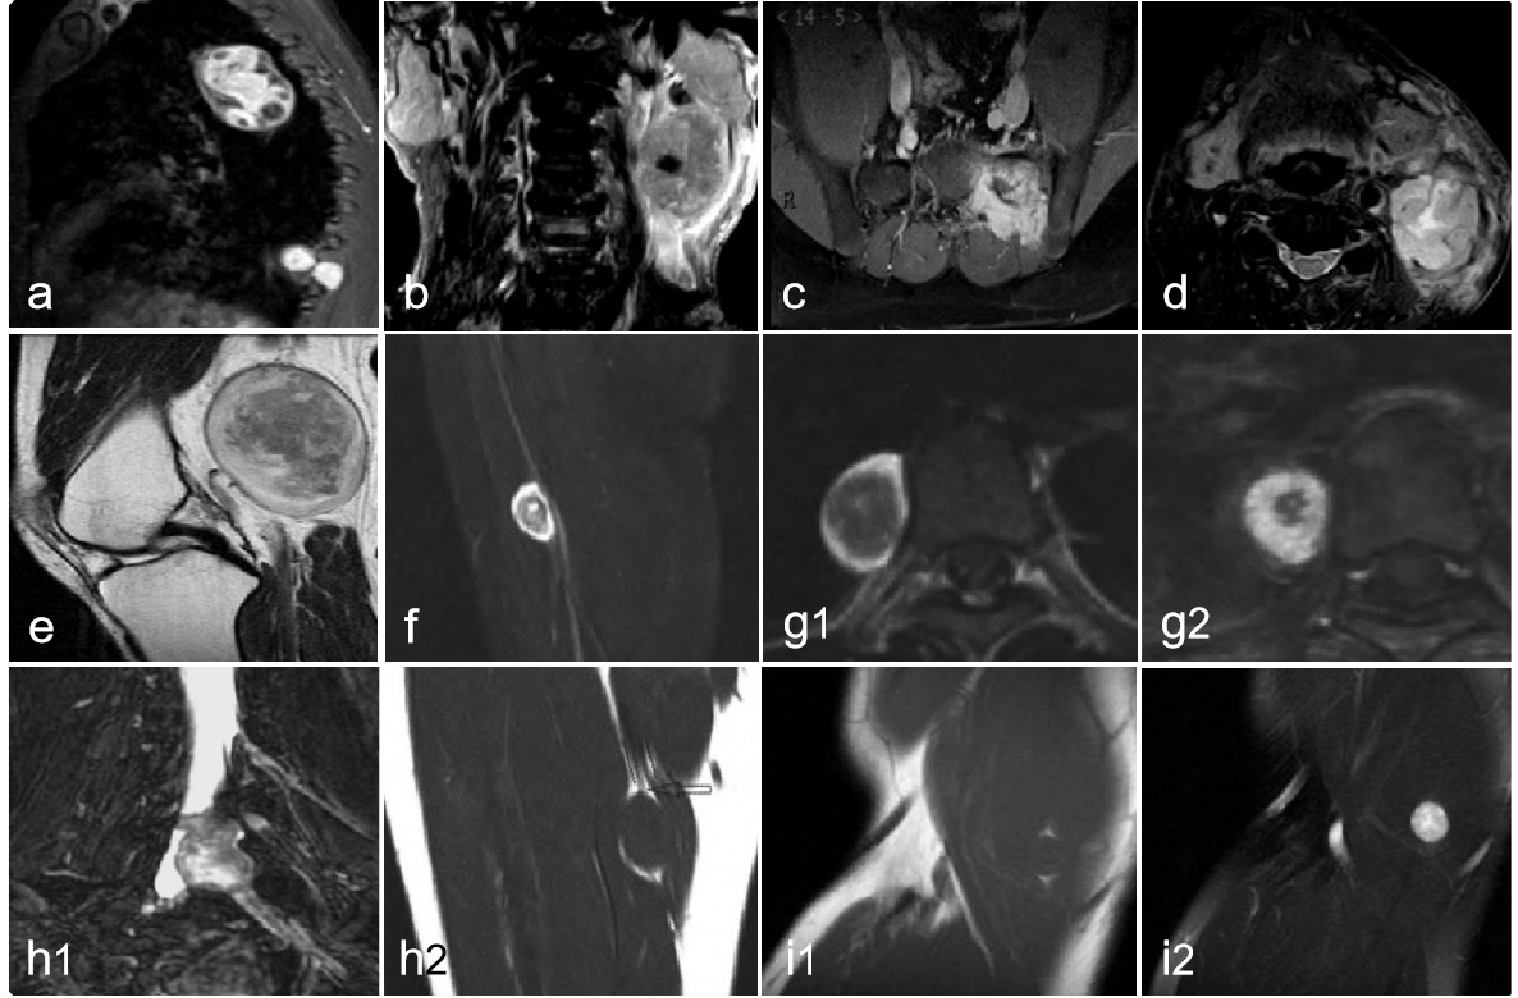

神经鞘瘤的MRI影像可有“形态呈梭形,包膜完整 、包膜下囊变 、中央裂隙征 、束状征 、靶征 、神经出入征 、脂肪分离征及强化点征、血管贴边征”等多个征象,其中以“包膜完整 、束状征及包膜下囊变”这 3 个 MRI 征象最具特异性。下图是全身多部位神经鞘瘤的典型MRI征象,可用于辅助学习腹膜后神经鞘瘤。

1cb7d55c23391da302d7e07c1a739bf1.png 图 44:神经鞘瘤(各部位)MRI典型征象a:“包膜下囊变征”,病灶包膜下多发大小不 、形态不定的无强化囊变区;b:“血管点征”,病灶内多发点状或管状的血管强化信号;c:“中央裂隙征”,病灶中心为裂隙状黏液变、囊变区;d:“束状征”,T2WI 示神经鞘瘤内及边缘多发条索状低信号神经纤维;e:“靶征”,T2WI 呈病灶外周高信号,中心等、低信号;f:“血管贴边征”;g1、g2:“典型靶征”;h1:“神经出入征”,MRN示神经鞘瘤的两极低信号A、B号神经出入;h2:箭头所指低信号的神经出入;i1、i2:“脂肪分离征”,病灶上下方小三角形脂肪信号,压脂后病灶上下方异常信号消失。